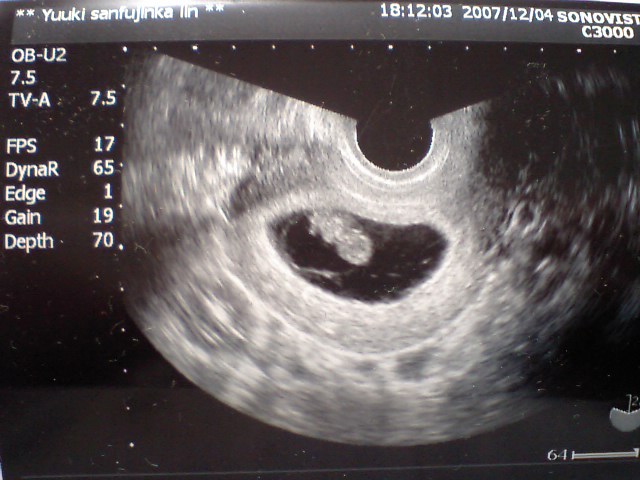

2008年7月9日 が予定日です

そして今回の写真~

←大きさ23ミリ

(一週間で6ミリの成長です)

心臓バクバク動いてました

前回と同じじゃん!とかっていわないでね。